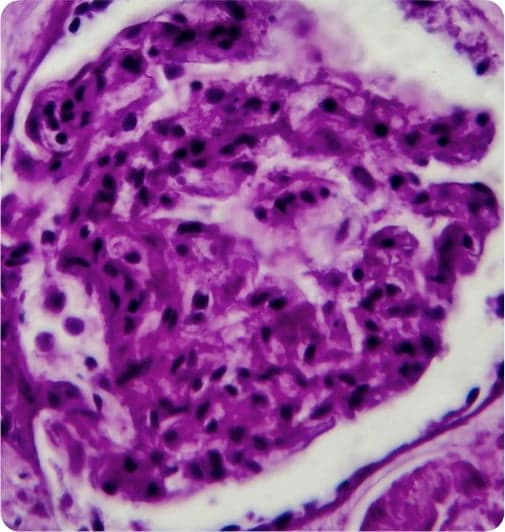

LUPUS NEPHRITIS

What it is

An autoimmune disease in which chronic kidney inflammation can ultimately lead to complete kidney failure and the need for renal replacement.

Where it strikes

Systemic lupus erythematosus is among the top 15 most prevalent autoimmune diseases in the U.S.1, affecting approximately 330,000 patients.3 Lupus nephritis (LN) affects up to 60% of patients with systemic lupus erythematosus (SLE). Up to 10% of patients with LN and 40% with diffuse LN (class IV) will ultimately develop kidney failure, requiring dialysis or a kidney transplant to stay alive.4

Current treatments

Two conventional approaches; one small molecule, and one biologic agent were recently approved by the FDA for the treatment of patients with active lupus nephritis in combination with a background immunosuppressive regimen. Despite these approvals there is still an unmet medical need for truly transformative approaches that will eliminate the use or need for potent immunosuppressants, dialysis, or kidney transplantation.